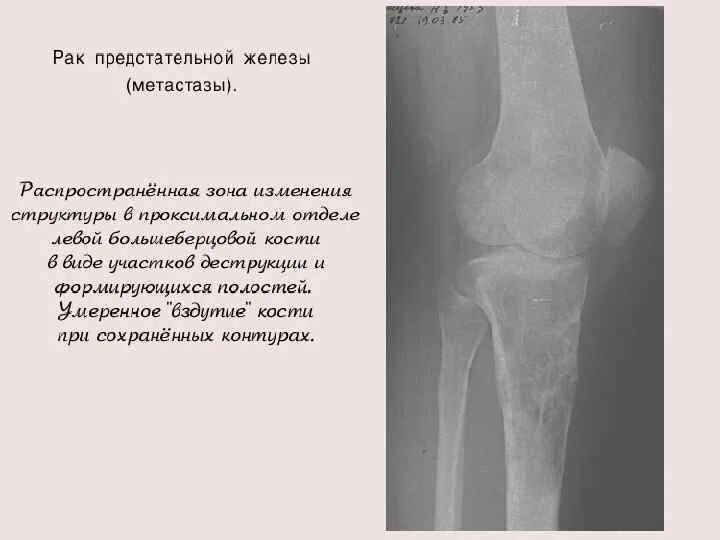

Метастазы в костях какая стадия